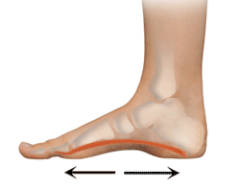

脚部受力异常:扁平足、高弓足,甚至走路姿势不正确等。

足弓支撑。医生可能会开个处方,使用现成的或定制的足弓支撑(orthotics)来将压力更均匀地分散到脚上。